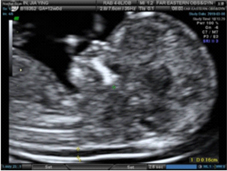

4D超音波影像

胎兒頸部透明帶超音波影像

高層次超音波影像